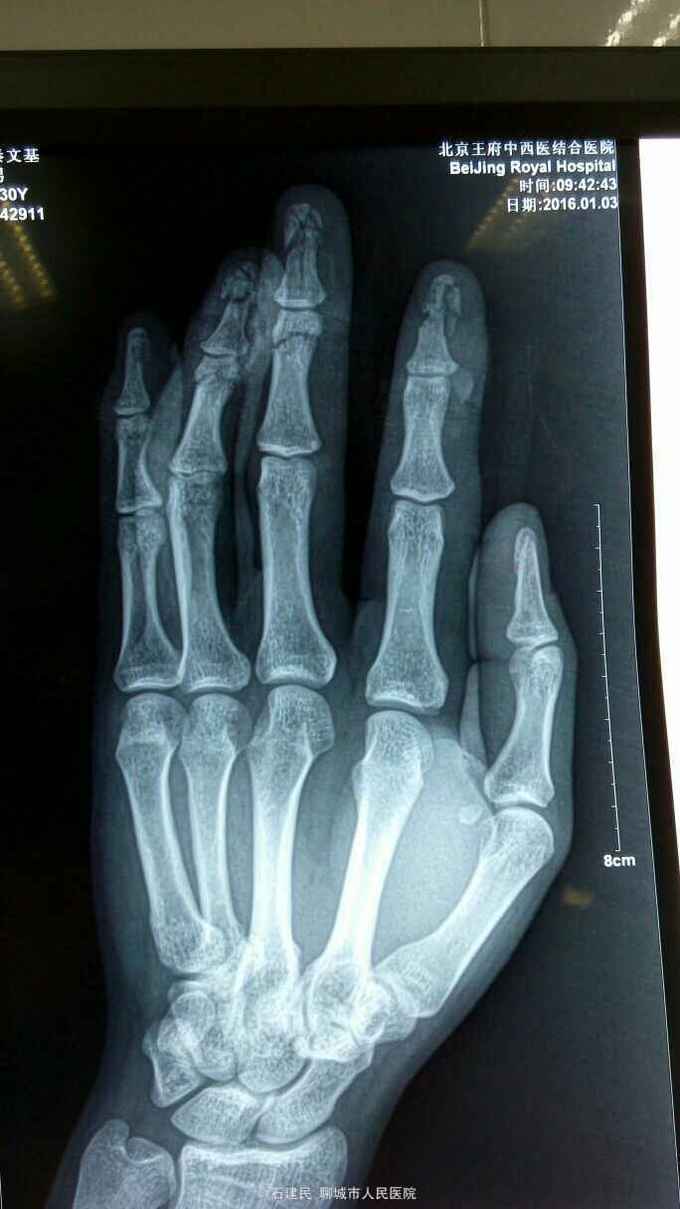

骨折 指骨骨折

压面机轧伤致左手肿痛不适,局部软组织挫伤污染,X线示示中环指多发指骨骨折,收住院治疗。

查体可见手部多处皮肤软组织擦挫伤,局部皮肤软组织裂伤,末节软组织肿胀明显。

诊断多发指骨骨折,软组织挫伤,给予闭合复位行克氏针内固定术,术中C臂透视位线良好。